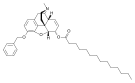

- Esters of morphine opiates: slightly chemically altered but more natural than the semi-synthetics, as most are morphine prodrugs, diacetylmorphine (morphine diacetate; heroin), nicomorphine (morphine dinicotinate), dipropanoylmorphine (morphine dipropionate), desomorphine, acetylpropionylmorphine, dibenzoylmorphine, diacetyldihydromorphine;[261][262]